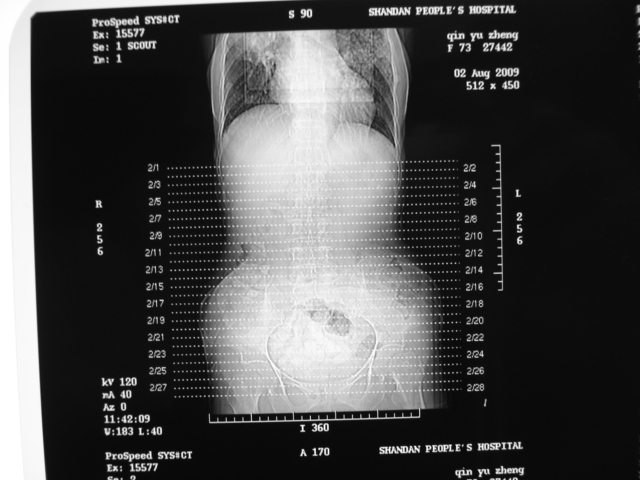

同事奶奶,73岁,腹痛一年,夜晚较重,潜血+++,拒绝增强,考虑左肾ca并腹膜后转移;请各位老师帮忙看看,谢谢!

左肾癌侵及输尿管上段,腹膜后多发淋巴结转移,脾脏钙化灶。至于潜血+++,要考虑消化道病变,本次ct片肠腔未见明显异常。

1)考虑左肾癌侵犯肾盂并腹膜后淋巴结转移。2)脾脏钙化灶。

查查一胸部,不除外肺癌伴左侧肾上腺,腹膜后淋巴结及左肾转移.

定位像见上肺野也很糟糕,支持7楼。